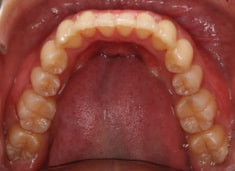

治療後(2年後)